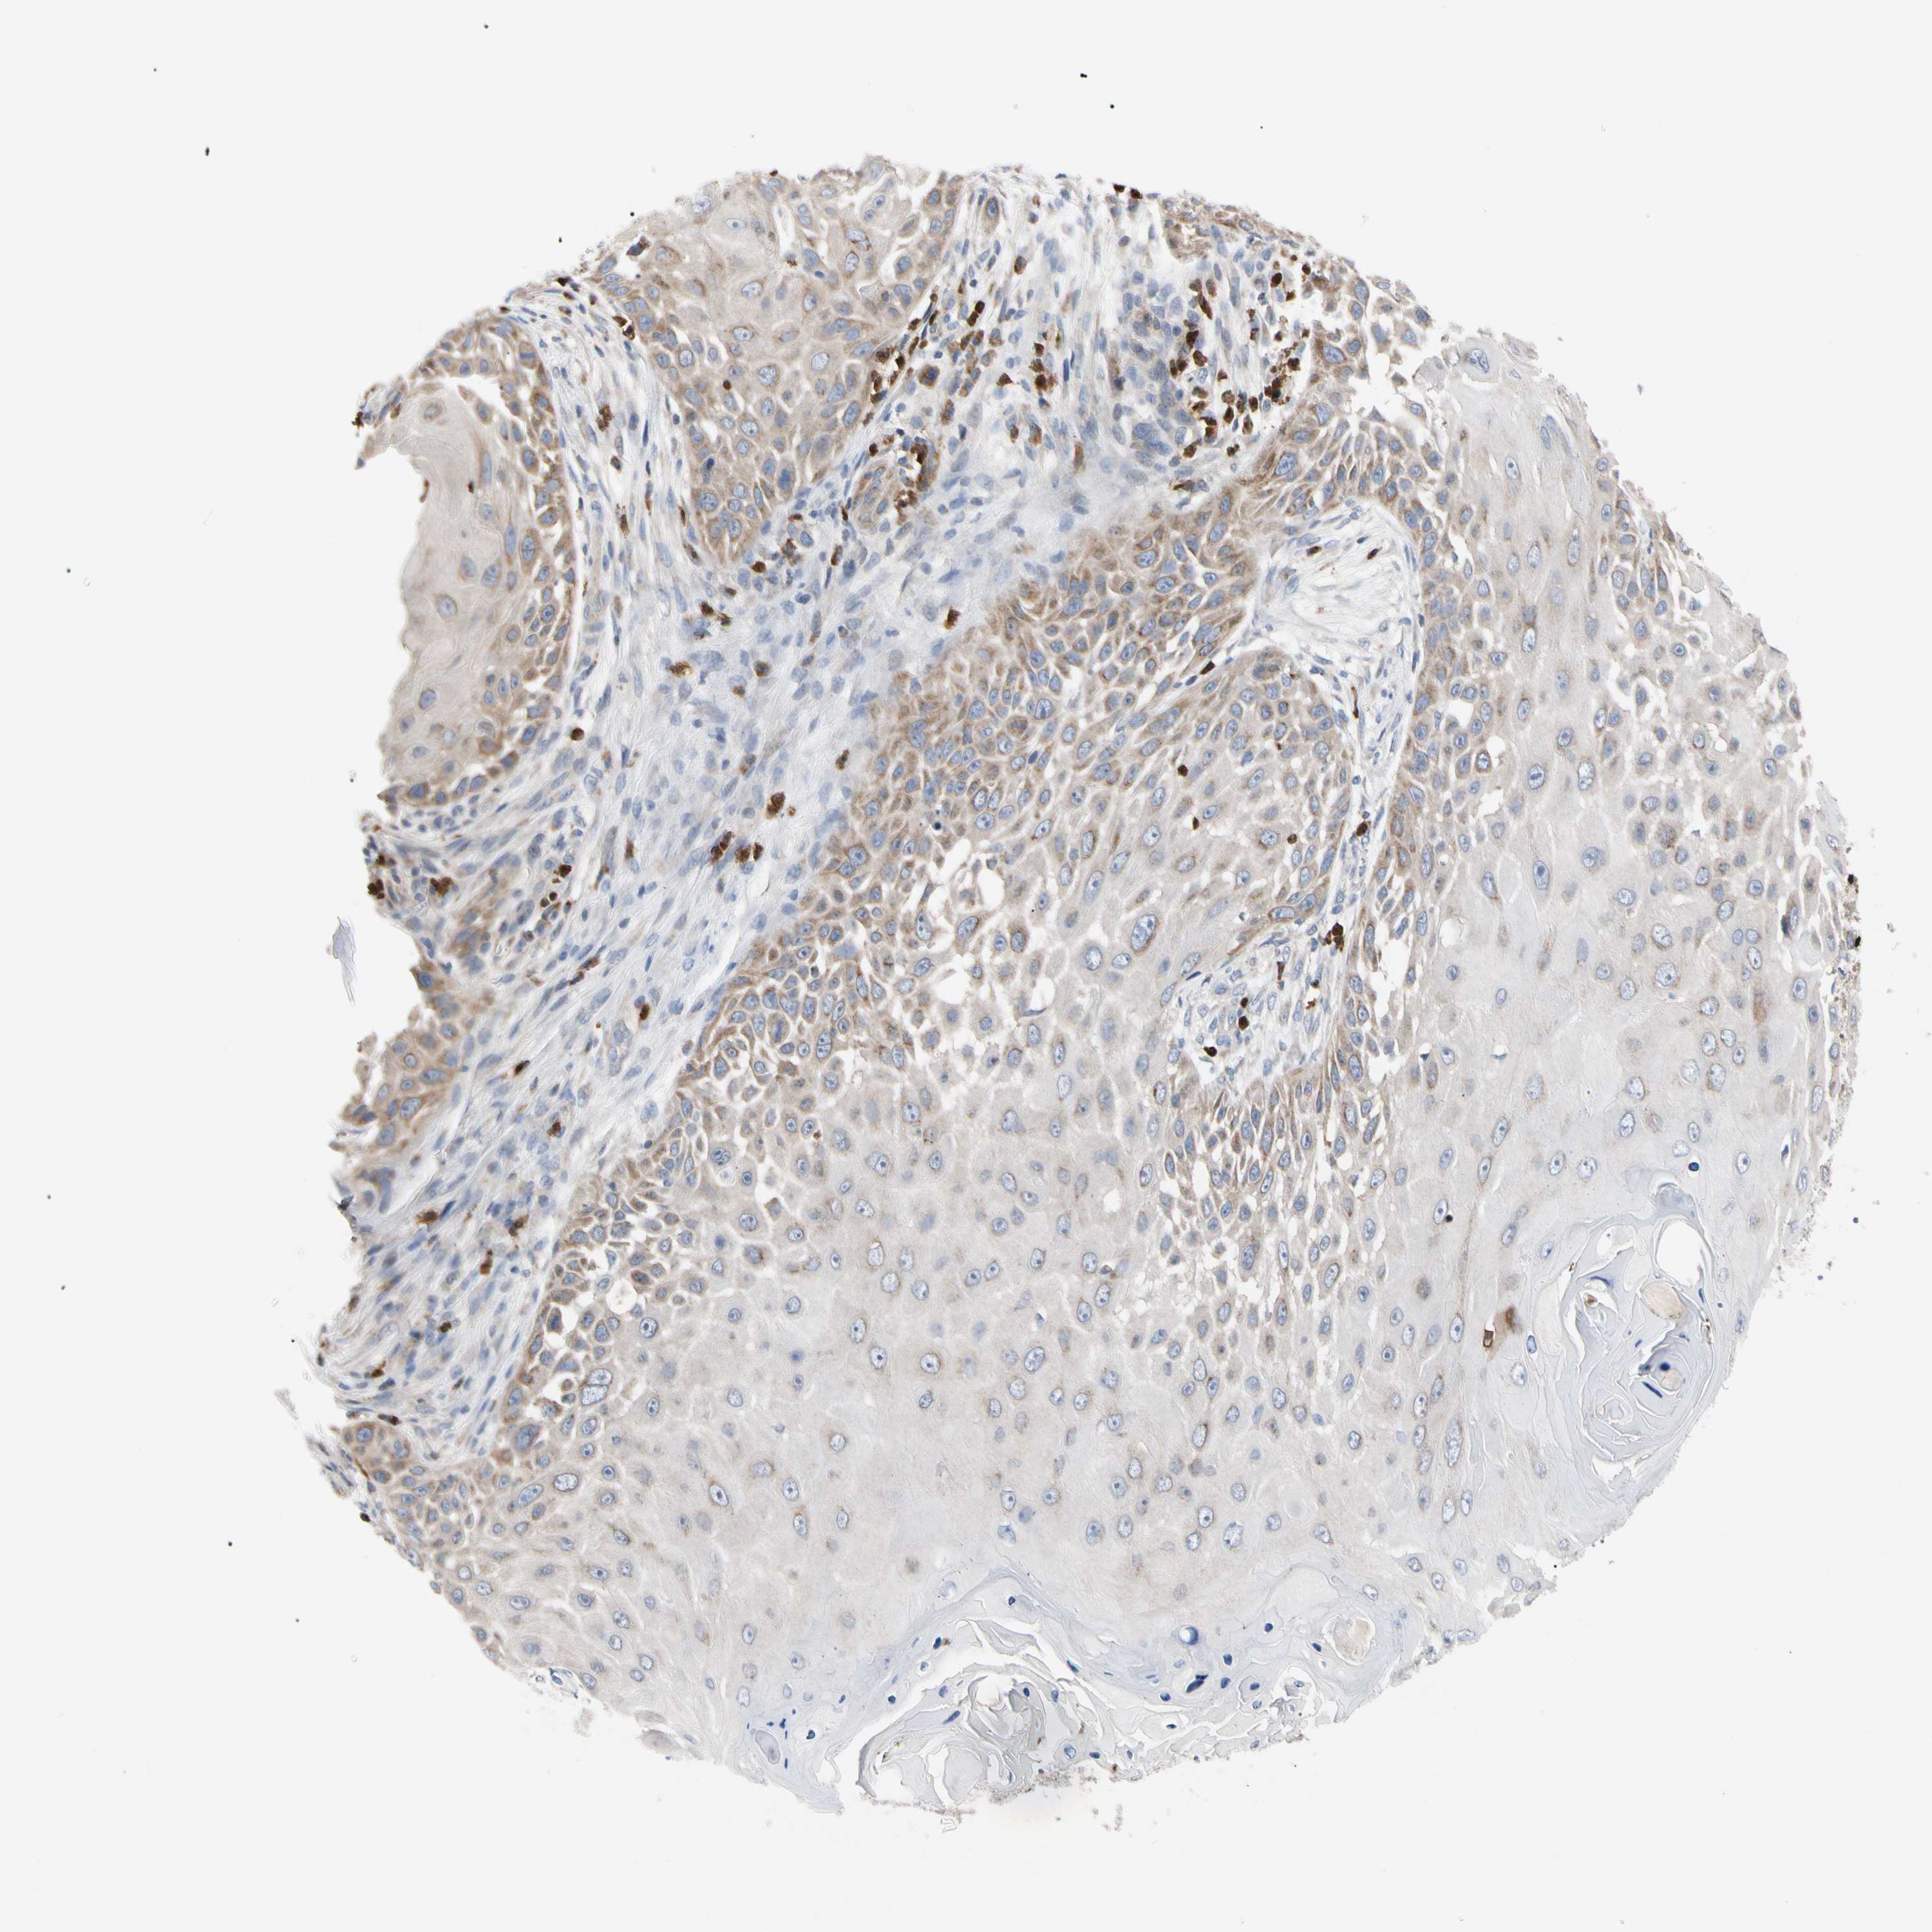

SKIN CANCER - Protein expressioni

A mouse-over function shows sample information and annotation data. Click on an image to view it in a full screen mode. Samples can be filtered based on level of antibody staining by selecting one or several of the following categories: high, medium, low and not detected. The assay and annotation is described here.

Antibody stainingi

Antibody staining in the annotated cell types in the current human tissue is reported as not detected, low, medium, or high, based on conventional immunohistochemistry profiling in selected tissues. This score is based on the combination of the staining intensity and fraction of stained cells.

Each image is clickable and will lead to virtual microscopy that enables deeper exploration of all samples and also displays staining intensity scores, fraction scores and subcellular localization as well as patient and tissue information for each sample.

Antibody HPA008455

Staining

High

Medium

Low

Not detected

Intensity

Strong

Moderate

Weak

Negative

Quantity

>75%

75%-25%

<25%

None

Location

Nuclear

Cytoplasmic/membranous

Cytoplasmic/membranous,nuclear

Squamous cell carcinoma, NOS

Squamous cell carcinoma, metastatic, NOS

Basal cell carcinoma

Papilloma, NOS